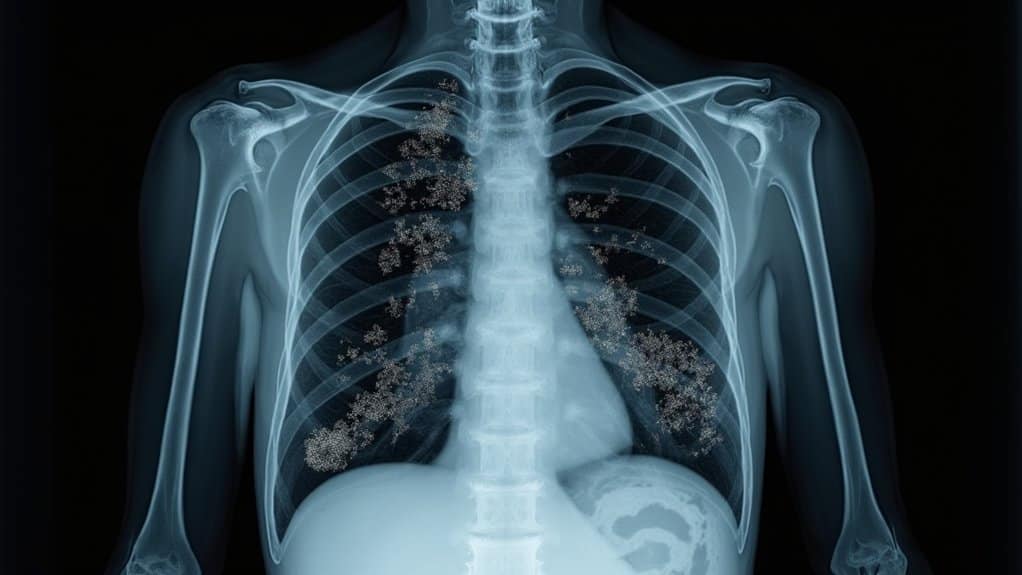

Doctors who’ve examined patients with crack lung symptoms report the lungs sound crackly, like someone crumpling up cellophane. In many diagnostic cases, a crack lung CT scan helps reveal how much damage has occurred and whether there are visible ground-glass opacities or scarring within the lungs.

To diagnose crack lung, CT scans and chest X-rays (CXR) are the fastest course of action for emergency departments, especially when the person is not honest about drug abuse. Crack lung CT scan and crack lung radiology images and crack lung CXR will show ground glass opacities (GGO), which appear like shattered or spun glass inside the lungs. GGOs show inflammation, fluid, puss, or scar tissue and help medical professionals figure out how severe the issue is and the best course of treatment.